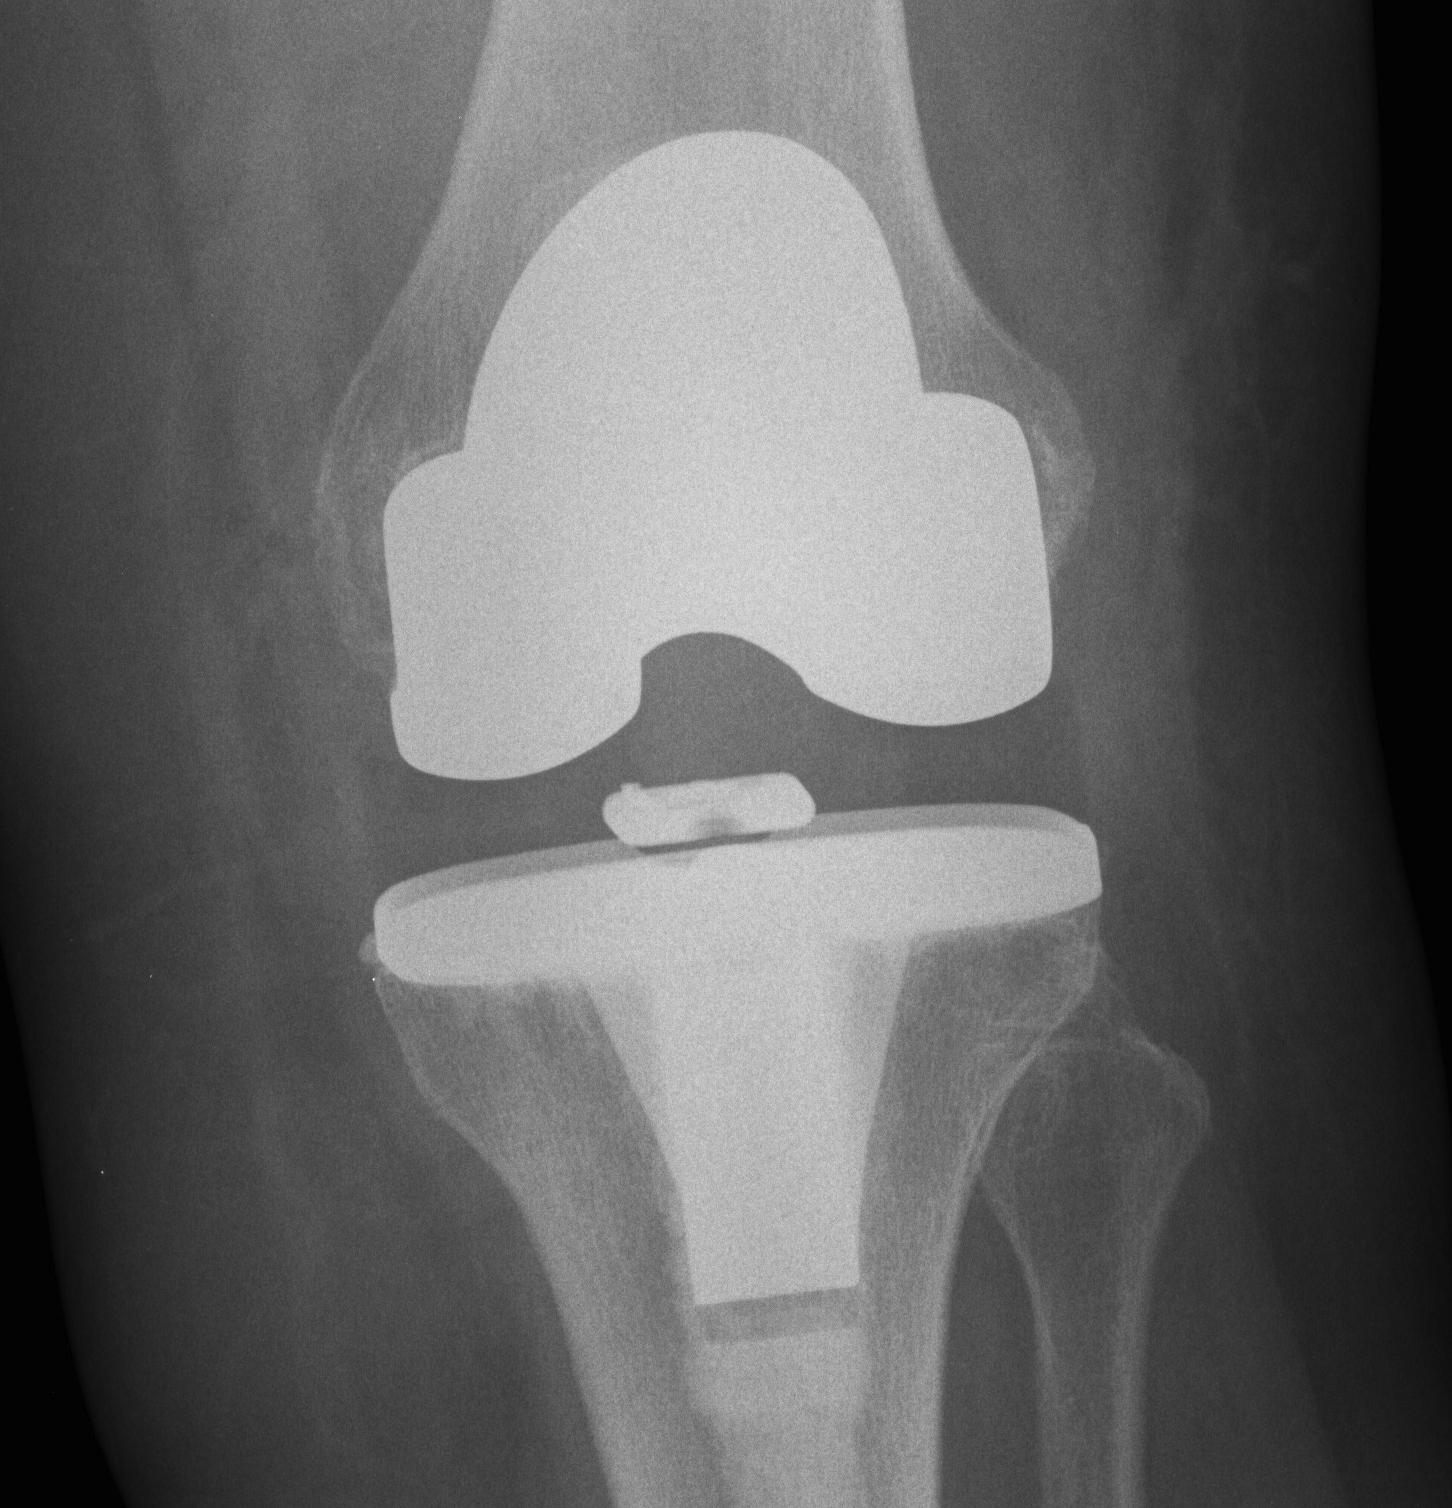

3. Global instability

Unstable in sagittal and coronal planes

1. Insufficient poly thickness / poly wear

Options

- increase poly thickness

2. Loosening / collateral ligament damage

- revise to highly constrained prosthesis